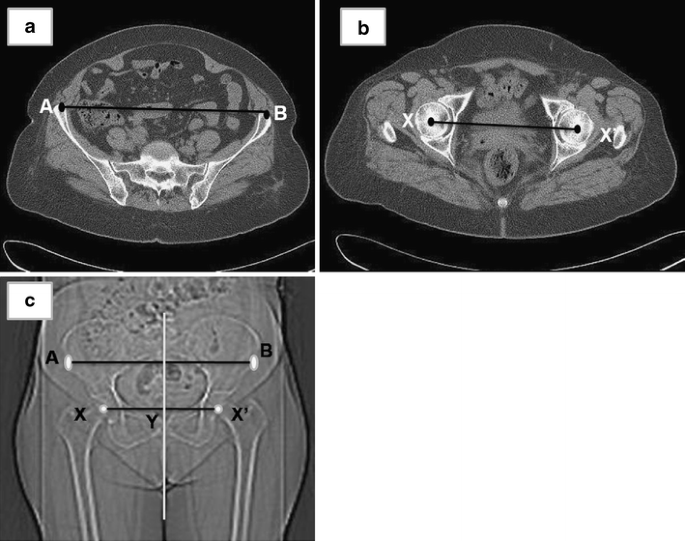

Accuracy Of Anterior Superior Iliac Spine Symmetry Assessment By Routine Structural Examination

Accuracy Of Anterior Superior Iliac Spine Symmetry Assessment By Routine Structural Examination from www.degruyter.com